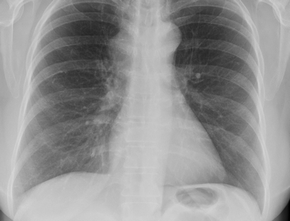

A 75-year-old female patient who presented with exertional dyspnea. You order a chest x-ray (Fig. 1a, b).

Figure 1. PA (a) and lateral chest x-ray (b).

Do you see an abnormality on the PA and lateral views?

The x-ray shows a large well-circumscribed, non-calcified mass (Fig. 2a) overlying the inferior left side of the chest. There are tubular elongated structures that appear to emulate from the mass coursing towards the left hilum. On first glance you may think that this mass is associated with the left breast. However, when you look on the lateral x-ray (Fig. 2b) you can see that this mass (arrows) lies posterior and by process of elimination can only lie within the left lung.

Figure 2. a, PA chest x-ray. A well-circumscribed, non-calcified mass (arrow) lies within the left lung.

Tubular elongated structures (arrowheads) are seen extending from the mass coursing towards the left hilum, b, lateral Chest X-ray. A well-circumscribed, non-calcified mass (arrows) lies posteriorly within

the left lung.